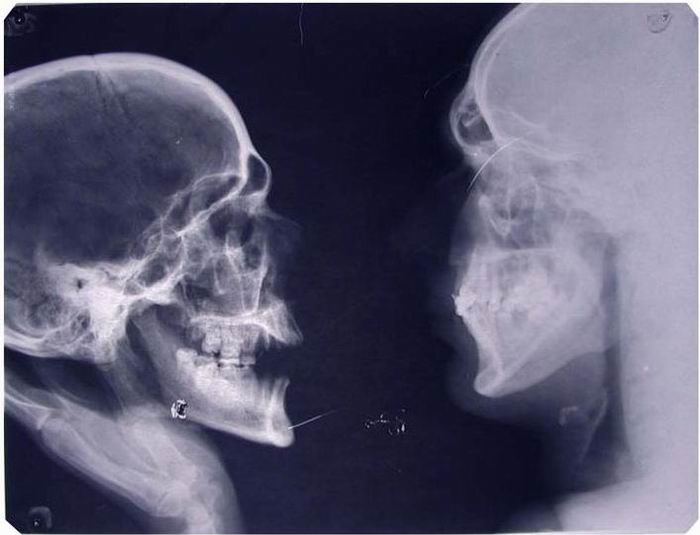

Смешные картинки и мемы ко Дню рентгенолога